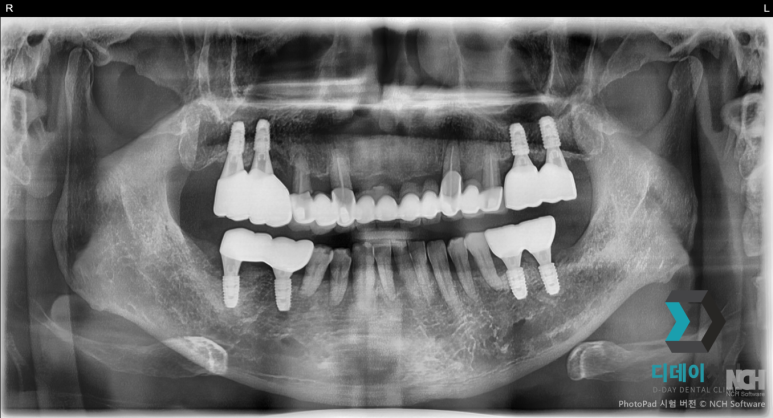

양쪽 위아래 심한 치주염으로 발치 후 즉시 임플란트 식립